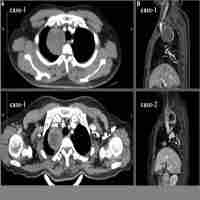

| Abstract | Background The authors presented a 63-year old female synchronously complicated with a thymic tumor located at the left-side of the superior mediastinum, and a paravertebral tumor located at the right-side of the lower thorax. Conventional thoracoscopic surgical procedure using rigid instruments to simultaneously resect the two tumors via the same ports might be technically challenging. To our knowledge, the use of a surgical robot allowed the surgeon to perform precise dissection from extreme angles with the characteristic of articulating surgical instruments. Case presentation Two lesions were successfully dissected using the da Vinci Surgical System through the same four ports on the right side of the chest and two-step docking. Firstly, the patient cart came from the dorsal side of the patient and the paravertebral neoplasm was dissected. Afterwards, the patient cart was undocked and the operation table was rotated 180 degrees counterclockwise. The robot was re-introduced and the patient cart came from the ventral side of the patient and the whole thymus was resected. Conclusion This case report suggests that two-step docking via the same four ports for these two tumors located at different directions of the thorax was safe and effective, demonstrating a clear advantage of the surgical robot. |